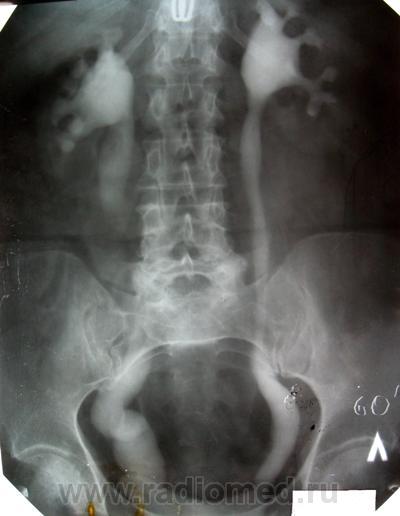

1. Имело место выпадение матки, все виденное - следствие этого прооцесса (кстати, больная была прооперирована, работает, а поступила сейчас с МКБ).

2. Если присмотреться к снмку на 27 мин стоя и на 120 к нижнему краю мочевого пузыря (хоть и под срез пленки), то кое что из этого можно было бы заподозрить.

4. Сегодня проведена в\в урография, двусторонний, больше справа, уретерогидронефроз сохраняется, динамика за 12 лет умеренно отрицательная. Д мочеточника справа до 4,0 см. Дистальные отделы мочеточников конусовидно сужены (слева видно лучше) на протяжении до 1,0 см или несколько более.

5. Прооанализировав повторно картину, оценив анамнез пришел к выводу о неправомочности первого вывода о причине изменений. Да, выпадение матки усугубило процесс, но он существовал и РАНЕЕ...очень много лет. Считаю, что имеет место АХАЛАЗИЯ мочеточников и, следовательно, Владимир Васильевич был прав. Вероятность того, что пусковым механизмом была ЧМТ весьма высок, хотя не исключаю и врожденный характер.